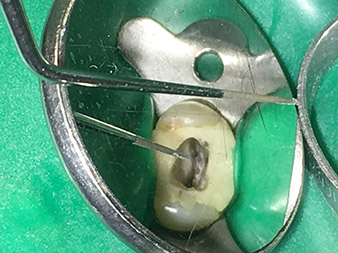

Dr. Nouraie: Yes, in my opinion. The tips allow you to work in a particularly atraumatic and minimally invasive manner. Among other steps, this applies to the exposure of the individual canal accesses, preparation of the cavity in the area of the pulp chamber, rounding off of the canal openings at the transition from the bottom of the chamber to the root canal and preparation of the coronal regions of the root canals.

The 4E tip – this instrument is optimally suited to preparation of the cavity floor at the transition to the canals. It can be used to round off the transition between the canal and the cavity floor optimally so as to produce a funnel leading into the canal. In addition, the instrument is the ideal choice for removing dentine overhangs from canals.

All in all, the cavity can be prepared very efficiently and minimally invasively with this tip by optimally rounding off and smoothing overhangs, corners and edges.

Pictures: Dr. Shahrad Nouraie Ashtiani, Bremen